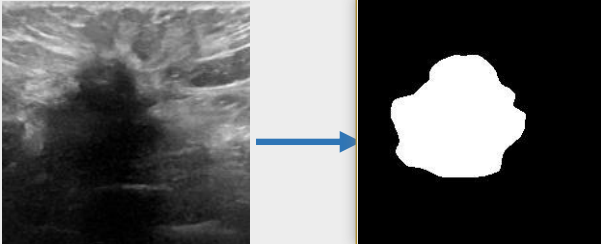

## 算法原理 U-KAN与其它图像分割算法一样,将图片数据送入模型后,依次通过预处理、特征提取,最后经过卷积预测出像素类别实现分割。

## 环境配置 ``` mv U-KAN-optimize_pytorch U-KAN # 去框架名后缀 # if torch>2.0, modify /usr/local/lib/python3.10/site-packages/timm/models/layers/helpers.py: from torch._six import container_abcs -> import collections.abc as container_abcs ``` ### Docker(方法一) ``` docker pull image.sourcefind.cn:5000/dcu/admin/base/pytorch:2.1.0-ubuntu20.04-dtk24.04.1-py3.10 # 为以上拉取的docker的镜像ID替换,本镜像为:a4dd5be0ca23 docker run -it --shm-size=32G -v $PWD/U-KAN:/home/U-KAN -v /opt/hyhal:/opt/hyhal:ro --privileged=true --device=/dev/kfd --device=/dev/dri/ --group-add video --name ukan bash cd /home/U-KAN pip install -r Seg_UKAN/requirements.txt # requirements.txt ``` ### Dockerfile(方法二) ``` cd U-KAN/docker docker build --no-cache -t ukan:latest . docker run --shm-size=32G --name ukan -v /opt/hyhal:/opt/hyhal:ro --privileged=true --device=/dev/kfd --device=/dev/dri/ --group-add video -v $PWD/../../U-KAN:/home/U-KAN -it ukan bash # 若遇到Dockerfile启动的方式安装环境需要长时间等待,可注释掉里面的pip安装,启动容器后再安装python库:pip install -r Seg_UKAN/requirements.txt。 ``` ### Anaconda(方法三) 1、关于本项目DCU显卡所需的特殊深度学习库可从光合开发者社区下载安装: - https://developer.sourcefind.cn/tool/ ``` DTK驱动:dtk24.04.1 python:python3.10 torch:2.1.0 torchvision:0.16.0 ``` `Tips:以上dtk驱动、python、torch等DCU相关工具版本需要严格一一对应。` 2、其它非特殊库参照requirements.txt安装 ``` pip install -r Seg_UKAN/requirements.txt # requirements.txt ``` ## 数据集 `BUSI(Breast Ultrasound Image)` - https://www.kaggle.com/datasets/aryashah2k/breast-ultrasound-images-dataset 本项目无需下载原始数据集,采用U-KAN作者提供的预处理数据[pre-processed dataset](https://mycuhk-my.sharepoint.com/:f:/g/personal/1155206760_link_cuhk_edu_hk/ErDlT-t0WoBNlKhBlbYfReYB-iviSCmkNRb1GqZ90oYjJA?e=hrPNWD) 即可。 项目中已包含[`busi`](./Seg_UKAN/inputs/busi.zip),解压即可使用,训练数据目录结构如下: ``` Seg_UKAN ├── inputs │ ├── busi │ ├── images │ ├── malignant (1).png | ├── ... | ├── masks │ ├── 0 │ ├── malignant (1)_mask.png | ├── ... ``` ## 训练 ### 单机单卡 ``` # 以公开数据集busi为基础进行算法效果优化 cd Seg_UKAN python train.py --arch UKAN --dataset busi --input_w 256 --input_h 256 --name busi_UKAN --data_dir ./inputs ``` 更多资料可参考源项目的[`README_origin`](./README_origin.md) ## result

### 精度 数据集:busi,max epoch为400,训练框架:pytorch。 | 算法 | Dice | |:---------:|:------:| | U-KAN | 78.75% | | U-KAN-optimize | 79.64% | ## 应用场景 ### 算法类别 `图像分割` ### 热点应用行业 `医疗,电商,制造,能源` ## 源码仓库及问题反馈 - http://developer.sourcefind.cn/codes/modelzoo/u-kan-optimize_pytorch.git ## 参考资料 - https://github.com/CUHK-AIM-Group/U-KAN.git - https://github.com/KindXiaoming/pykan.git - https://kindxiaoming.github.io/pykan/